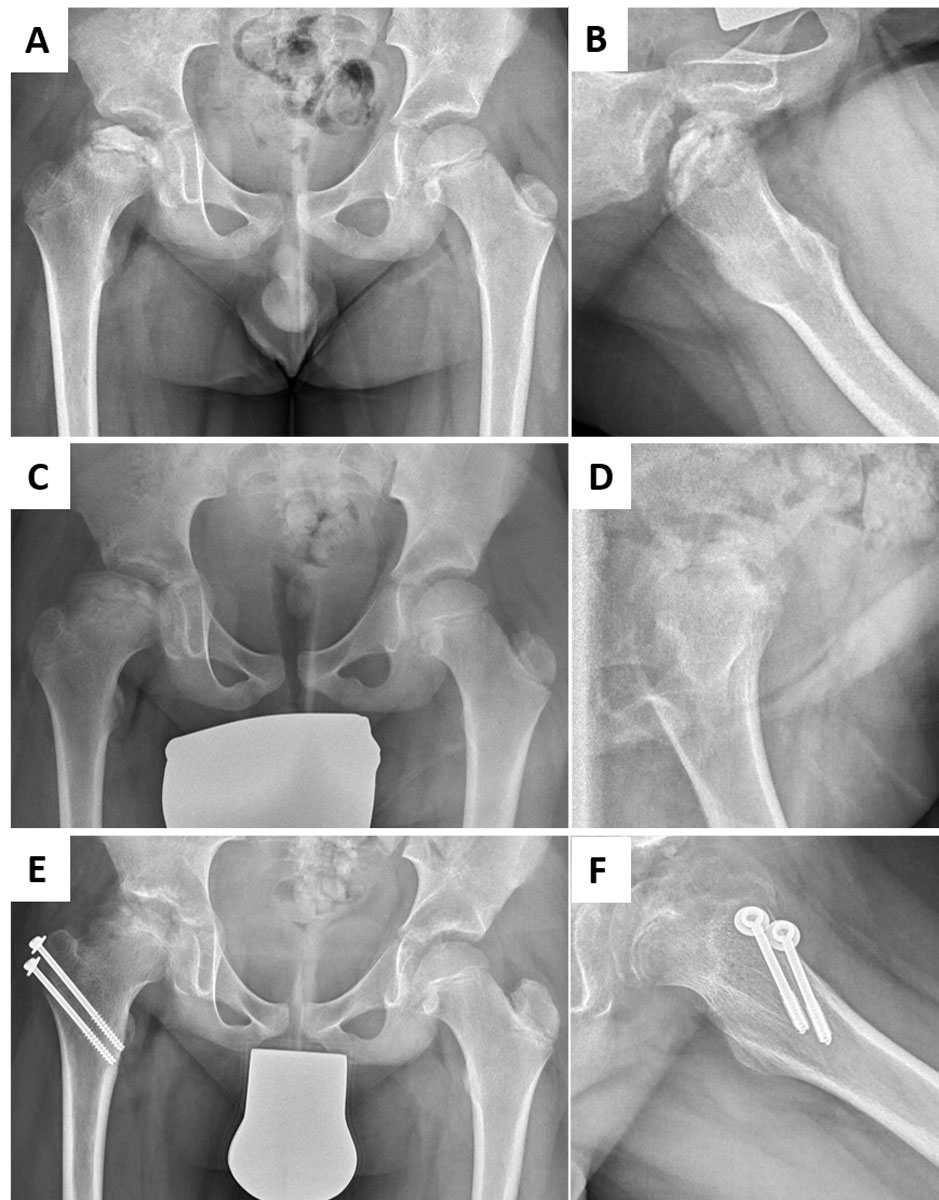

Osteochondral defects of the lower extremity can impact children’s mobility, and participation in leisure activities and sports in particular. Legg-Calvé-Perthes is a typical paediatric disease in this category, with the peak onset of symptoms between 5 and 10 years of age. The exact aetiology remains elusive, but compromised vascularisation and repetitive mechanical stress, amongst others, are discussed as potential causes. The disease can lead to subchondral fractures of variable severity, and eventually to complete destruction of the femoral head [13, 28]. Affected children are characterised by a shortened leg and functional impairment with limping. Moreover, incongruent articular surfaces at skeletal maturity are strongly associated with premature osteoarthritis of the hip joint [29]. Existing treatment modalities depend on the patient’s age and the stage of the disease. In younger patients or mild cases, observation, bed rest or medication with anti-inflammatory compounds, bisphosphonates or bone morphogenetic proteins have been used with success. In more severe cases, surgical treatment is necessary, with greater trochanteric epiphysiodesis to compensate for loss of epiphyseal height (fig. 2), or derotational osteotomy of the femur or osteotomy of the acetabulum, with the aim to protect the weak fragmented head from deformity [30]. Reconstruction of such osteochondral defects with tissue engineered grafts could restore articular congruence and delay or even avoid early osteoarthritic changes. However, to date no reports of the implantation of engineered osteochondral composite solutions have been identified.

Figure 2 Osteochondral lesions at the hip site following Legg-Calvé-Perthes (LCPD) disease. (A, B) Radiographs in anteroposterior or Lauenstein projections of the hips of a 7-year-old boy with LCPD of the right hip (Catterall Group 4, Lateral Pillar Group C), indicating femoral head containment. (C, D) Radiographs in anteroposterior or Lauenstein projections taken at 15-month follow-up confirm acceptable containment with an enlarged but spherical femoral head after non-surgical treatment. (E, F) Radiographs in anteroposterior or Lauenstein projections 20 months after greater trochanteric epiphysiodesis at the age of 11 years, implemented to compensate for loss of epiphyseal height and abductor strength and to alleviate pain. The risk of developing early-onset osteoarthritis remains increased.